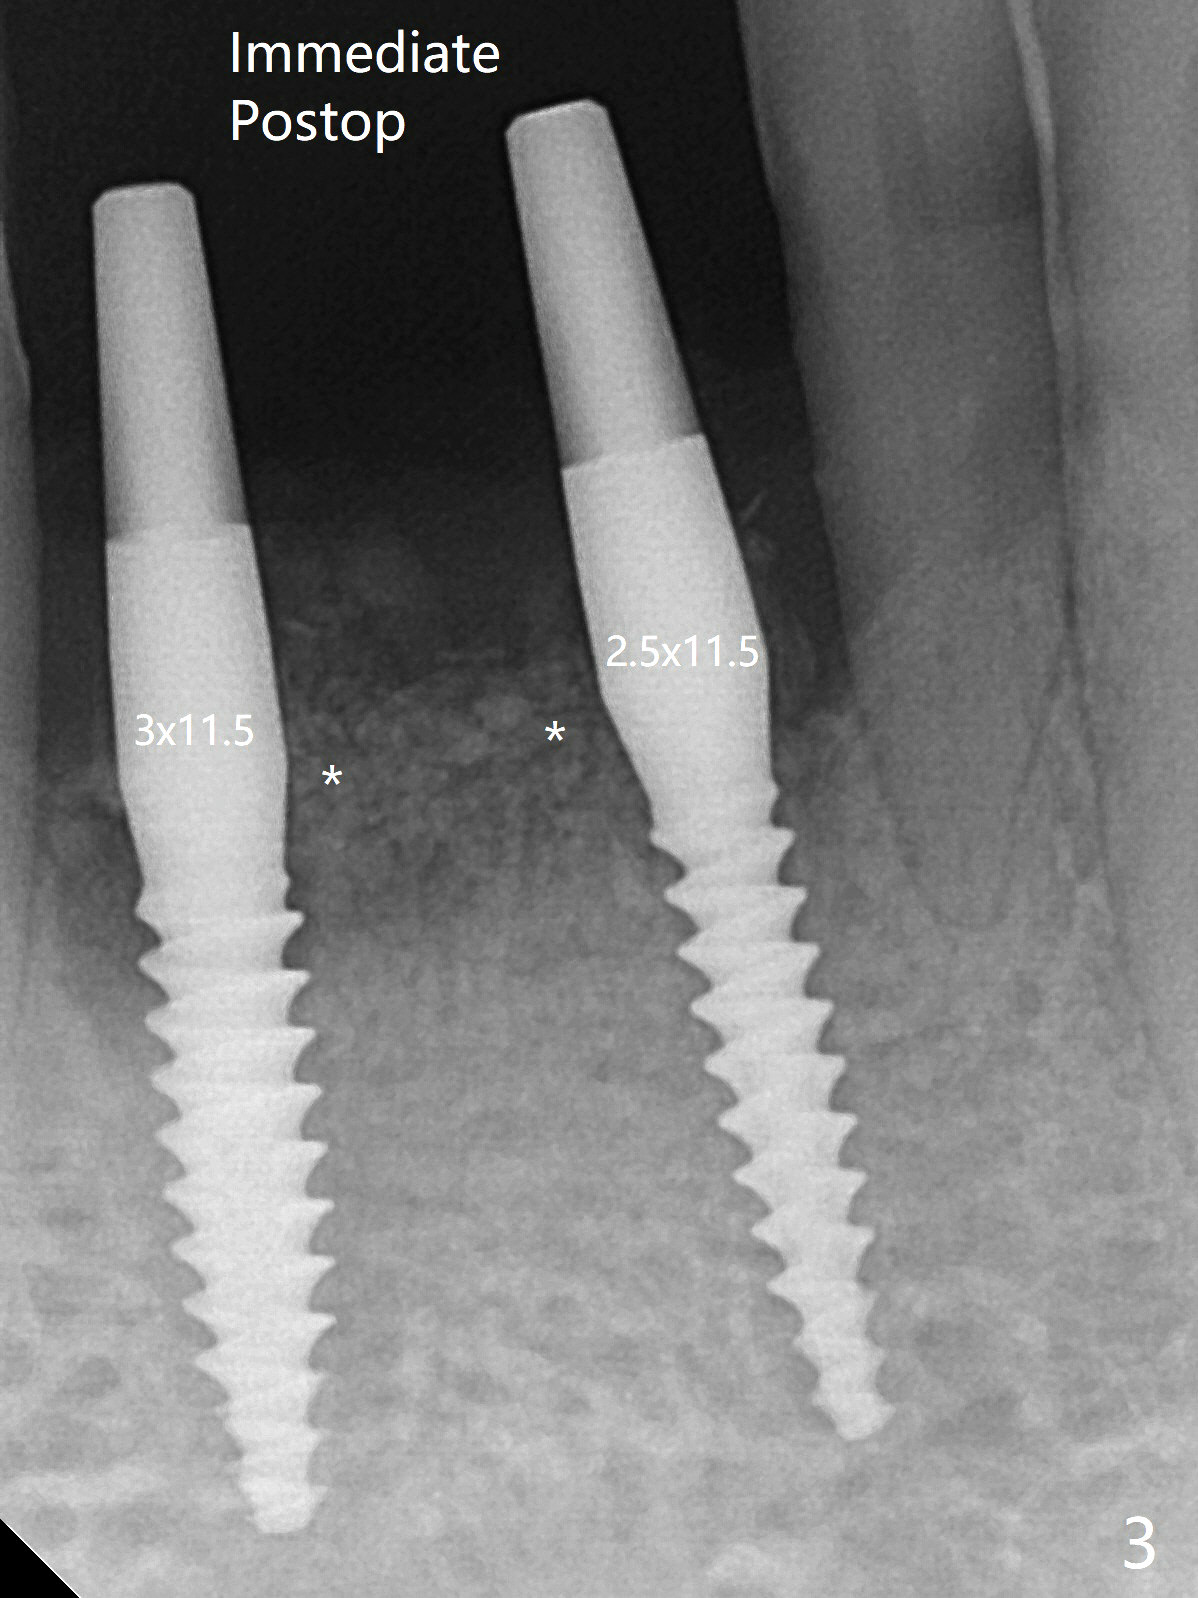

After placement of implant at #30 with high torque, osteotomy is prepared with 2.2 mm drill at #24 (M) first (Fig.1 before flap surgery). A 2.5 mm mini implant is placed < 10 Ncm (Fig.2,3). Since the ridge at #26 is apparently wider than that of #24 (Fig.1), a 3x11.5 mm implant is placed after the same drill (2.2 mm); insertion torque is ~ 35 Ncm. Bone graft is placed around the implants (Fig.2,3 *) before placement of PRF membrane. The patient is unpleased with our being unable to fabricate an immediate provisional (because of low torque at #24) as we have promised to. He is going to attend a wedding in fortnight. Instead periodontal dressing is applied. The latter is slight loose 1 week postop (Fig.4). There is apparently no bone loss 4 months postop with ~ 3 month provisional (Fig.5). The gingiva is healthy in spite of poor oral hygiene.